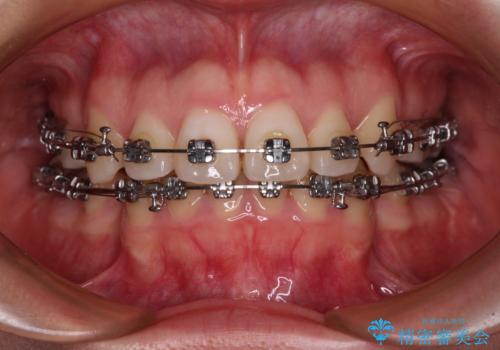

- メタルブラケット

- 2年4ヶ月

上下前歯がくちばしのように突出していましたが、抜歯矯正により口元が引っ込み、唇が閉じやすくなり、鼻の下の膨れた感じも解消されました。